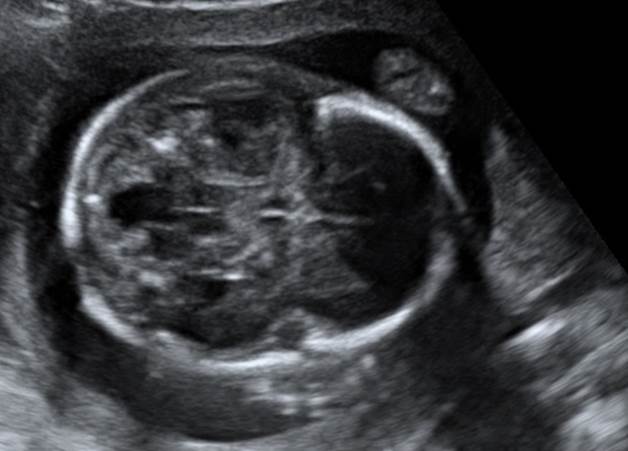

Вопрос 3

Попробуйте перечислить все изменения, который вы видите. 21 неделя. Что порекомендуем?

Ответ на вопрос 3

- Микрогнатия, аномалия Денди-Уокера стеноз клапана легочной артерии с гипертрофией миокарда правого желудочка.

- В данном случае по кариотипу мы получили трисомию 18, то есть синдром Эдвардса.